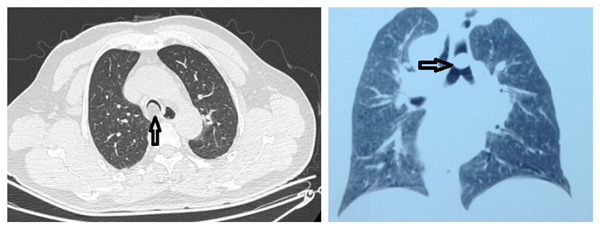

胸外科收治的患者男性,58岁。咳嗽、气短、憋气伴喘鸣1年余。多次复查胸部X线未见明显异常。入我院门诊行胸部CT提示气管膜部近隆突处低密度肿瘤,占据气管4/5,并突向气管后方脂肪间隙。行三维重建亦考虑脂肪瘤可能。

收入院后积极完善相关检查,行支气管镜检查示近隆突气管膜部可见似脂肪物突入管腔,包膜完整,表面光滑,基底较宽,距隆突距离不足1cm。请呼吸内科教授会诊亦考虑气管脂肪瘤可能,因基底较宽不建议行支气管镜下激光切除。麻醉科吕建瑞教授、张小琴教授与胸外科周斌主任、李少民教授及全科医生反复讨论后,一致决定,虽然气管肿物手术难度较大,但是病人病情危重,肿物堵塞管腔80%以上,随时有窒息的危险,如可以手术切除,则预后良好。给予病人及家属充分沟通后,病人同意了手术方案。